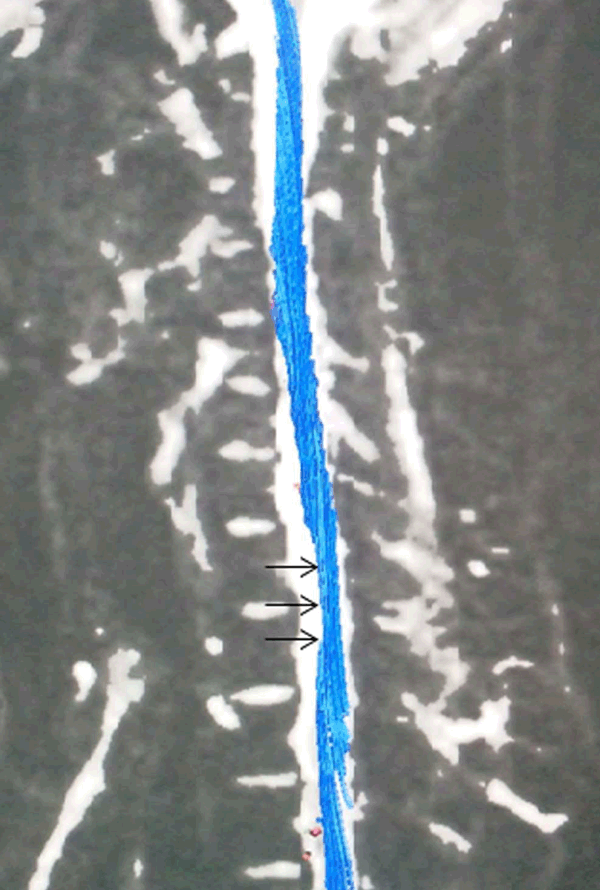

A 28-year-old male patient presented with progressive weakness of both forearms and hands along with clawing of hands for past eight years. Right side was affected more than the left. There was no history of similar illness in the family. There was no past history of any prolonged illness in childhood. There was no history of sensory, pyramidal or bladder dysfunction. There was atrophy of muscles of both forearms and hands. Muscle power was normal in both upper limbs. Nerve conduction studies showed reduced amplitude in bilateral median and ulnar nerves. Tendon reflexes were normal. Magnetic resonance imaging (MRI) examination was performed in non-flexion and flexed position. Subsequently, diffusion tensor imaging (DTI) was performed in non-flexion, which very clearly showed the cord atrophy at C7–T1 level. (Figure 1) This cord atrophy was not appreciated on MRI flexion and non-flexion studies. The diagnosis of Hirayama disease (HD) was thus established on DTI. | ||||||

Hirayama disease (HD) is a non-progressive, juvenile, spinal muscular atrophy of distal upper limbs and is a kind of cervical myelopathy related to flexion movements of the neck. Imbalance in growth of vertebrae and dura mater causes a loss of normal dural slack in extension. As a result of this, the tight dural canal causes compression of the spinal cord. [1] It is suggested that HD might be due to microvascular changes following chronic trauma to spinal cord during flexion and extension of the neck. [2] On non-flexion MRI studies, asymmetric cord atrophy especially at the lower cervical level is highly suggestive of HD. [3] Furthermore, the magnetization and diffusion MRI histograms of the cervical cord suggest that the cord damage in HD extends beyond that seen on routine MRI scans. [4] In our opinion, this atrophy of the spinal cord is best demonstrated on diffusion tensor imaging. This makes diffusion tensor imaging a valuable tool in diagnosing Hirayama disease without subjecting the patient to a flexion study of the cervical spine. | ||||||